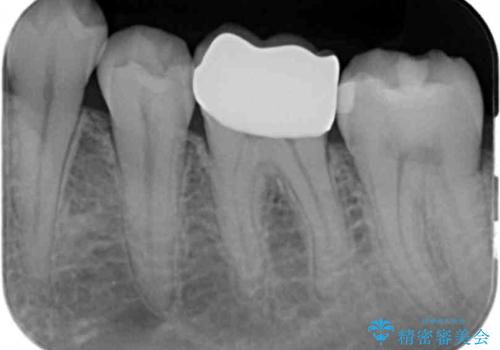

同じ樹脂の材料で詰め直しをしたところでまた変色してしまうリスクが高いため、セラミックでの治療となりました。

- 左下6 仮歯+セラミッククラウン 11000円+110000円費用は治療当時の料金となります